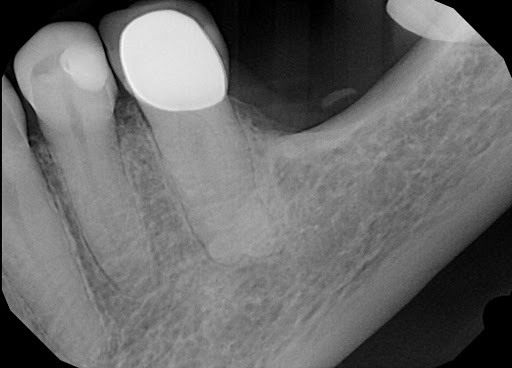

Above in the picture on the left is a tooth that has been prepared for a crown. All the decay the tooth had was removed and then a base of tooth was made from enamel colored filling material. Above on the right is an x-ray showing the buildup fully restored with the crown in place.

In this picture, there is a crown made of porcelain fused to metal. After preparing a tooth for a crown, impressions were taken, so the laboratory could make this restoration fit properly in the patient’s mouth.